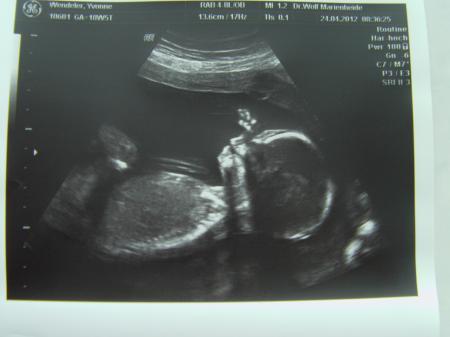

Hallo meine Lieben Also ich war ja vorhin beim Doc zum US.Nach 10 min. kamen wir auch dran.Dem Baby gehts soweit gut,doch war eine Auffälligkeit festzustellen! Im Hirnwasser wären wohl Zysten vorhanden,was aber nicht weiter besorgniserregend ist,da die bis zur 24.Woche wieder verschwinden.Ich soll daher nochmal in 5 Wochen zum US kommen und nachsehen lassen.Jetzt geht mir natürlich der Arsch auf Grundeis! Ich hab echt Angst.Was passieren könnte,wenn es nicht weggeht,weiss ich nicht...wollte es aber auch nicht wissen...Der Doc klang aber so als sein "nicht von bedeutung" aber er müsse es nunmal erwähnen. Sooo...nun zum outing : ... Nachdem er "Stundenlang" geschallt hatte,fragte ich dann mal was es denn wird.Und er meint zu 95-98 % eine Prinzessin :) Hat mir auch auf Anfrage die Scheide gezeigt und deutete auf die zwei weißen Striche :) später hat er nochmal inder richtung geschallt und dann sah ich es noch deutlicher! Juhuuu eine kleine Maus :D Ich bin so happy !!!!!!! Was ich nicht wusste...er hat 3D Ultraschall und hat kurz draufgeschaltet...aber die kleine hatte beide im Hände im Gesicht :) Zicke :D Ich bin so glücklich nach zwei Lausbuben endlich eine kleine Tochter :) Aber getrübt ist die Freude doch ein wenig :( Ich hoffe so sehr das sie gesund ist :/

Ich hoffe Ihr habt recht :/ Noch ein Bildchen von der kleinen :) Ich hoffe ich kann mich auf das outing verlassen :)

Bild zu